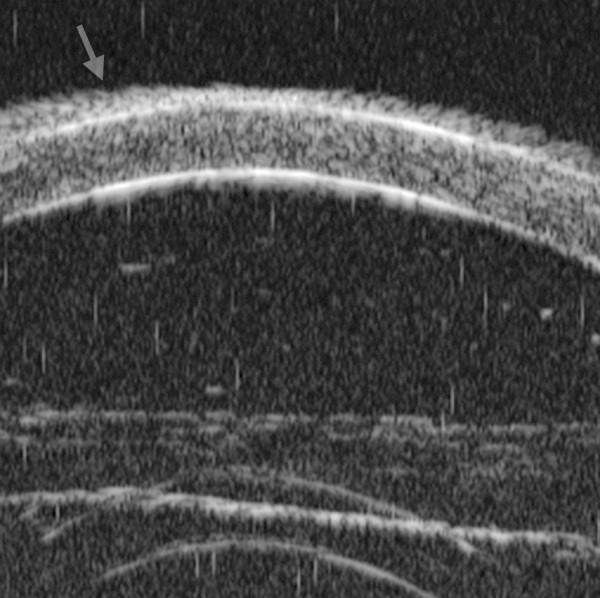

Ultrasound biomicroscopy (UBM) is a high-resolution ultrasound technique that allows noninvasive imaging of structural details of the anterior ocular segment at near light microscopic resolution and provides detailed assessment of anterior segment structures, including those obscured by normal anatomic and pathologic relations. This review gives an overview regarding the instrument, technique and its applications.

超声生物显微镜(UBM)是一种高分辨率超声技术,它能够以接近光学显微镜的分辨率对眼前节结构细节进行无创成像,并对眼前节结构进行详细评估,包括那些被正常解剖和病理关系所掩盖的结构。本文综述了该仪器、技术及其应用。